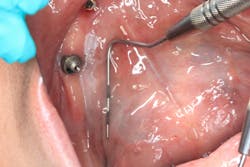

Patient: 40-year-old male

- 12 mm x 24 mm fluctuant mass on the lingual side of the left mandibular jaw, inferior and lingual to where no. 17 would be, along the palatoglossal arch muscle

- Tender to palpation

- Tissue in the surrounding area is normal in color

- No opposing dentition or history of trauma to the area